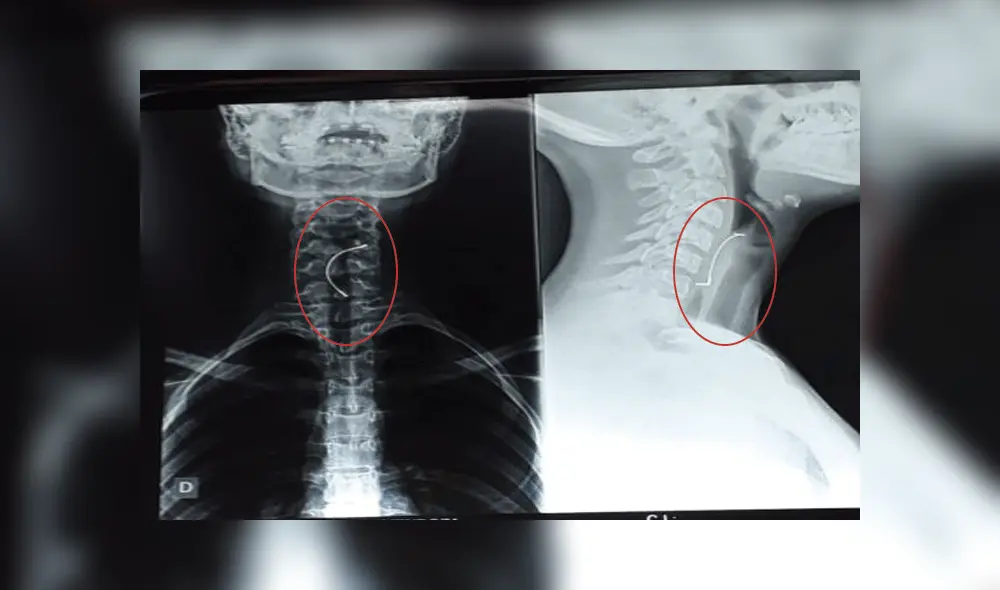

Radiografía de tórax de la menor.

Tras el hecho, ocurrido en Paraguay, la joven pudo salvarse, pese a que los especialistas decían que no se podía hacer nada más, pues el expansor de paladar había horadado la tráquea.

Una joven de 15 años sufrió un terrible accidente: mientras almorzaba en su vivienda de Paraguay, se tragó el expansor de paladar que usaba para su tratamiento de ortodoncia.

Asustada la joven decidió contarle lo sucedido a su mamá por lo que esta, la llevo de inmediato al hospital de Villarica. Aquí los doctores le dijeron que su accidente había sido grave, pues el objeto puntiagudo había perforado la tráquea y ya no se podía hacer nada por ella, según informaciones del portal web Extra de Paraguay.

Sin embargo, cuando las esperanzas se estaban acabando, la joven vomitó y el objeto subió hasta su garganta, tras esta acción los médicos realizaron una nueva radiografía y dijeron que con una endoscopia podrían sacar el expansor.